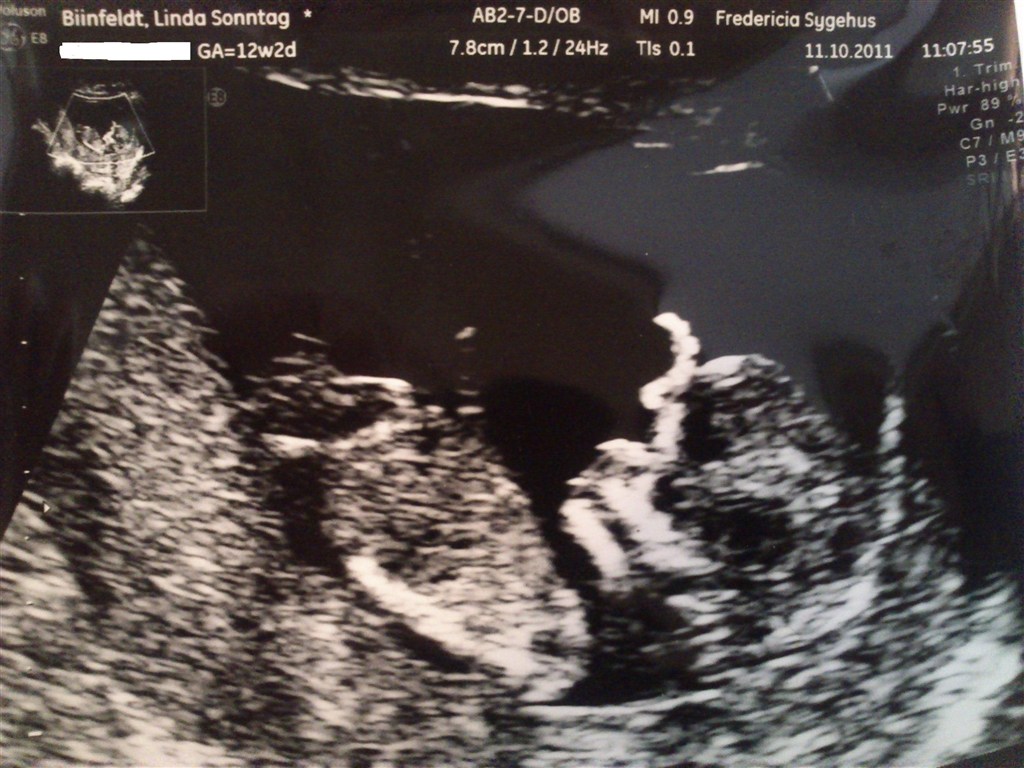

Jeg skal til misdannelsesscanning d. 8 dec. og jordmoder her d. 18 nov. Har lige været til kønsscanning på privatklinik idag. Det var ingen tvivl om at det var en lille dreng der lå derinde. En lille fodboldspiller er han, han sparkede helt vildt :O hehe